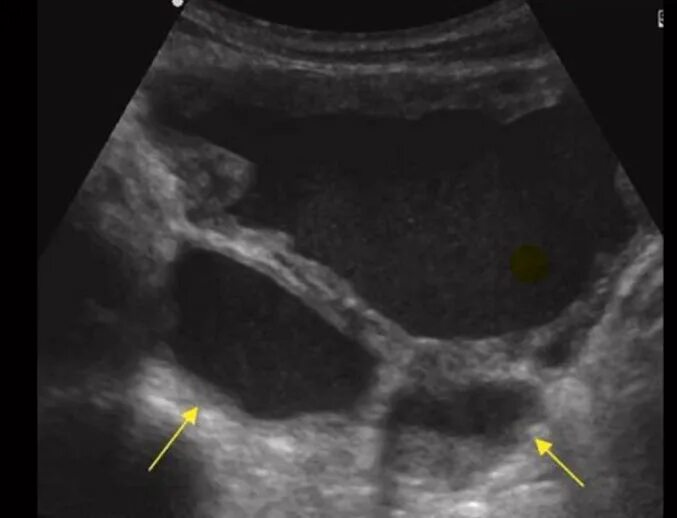

Дивертикул мочевого пузыря что это такое